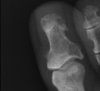

I have attached x-rays, recent photos of her toe and an MRI image from June. The nail is growing at an angle toward the distal phalanx. I believe the nail is growing closer to the bone since it was narrowed and it is exerting more pressure against the bone. She has a spur on the medial proximal base of the distal phalanx (visible on a magnified view of the oblique x-ray image). She also has an enlarged medial distal tuft of the distal phalanx. I believe the tuft is enlarged and it is approximating the distal medial nail border. In some people, this bone would not be a problem. With a deep ingrown toenail growing toward the bone where the nail has been narrowed, the bone could be too large for her. The lateral toenail border is ingrown, but it is growing away from the bone. She has typical pain there consistent with an ingrown toenail.

Boy, is this a tough one. You may be right, removing the exostoses may help. But they don't look very large, and the nail isn't humped in the usual way for a regular subungual exostosis.